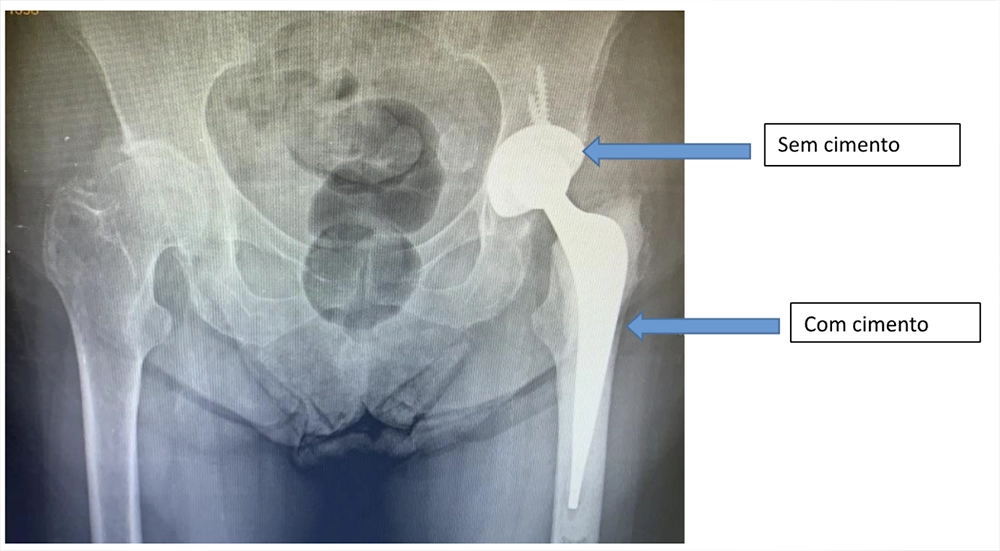

Exemplo de prótese total de quadril híbrida esquerda.

Existem no mercado diversos modelos de prótese de quadril para cirurgias primárias e revisões. Neste artigo, irei abordar os 3 principais tipos de próteses primárias realizadas: a não-cimentada (figura 3), a cimentada (figura 2) e as próteses híbridas onde geralmente o fêmur é cimentado e o acetábulo não cimentado (figura 4). A utilização de cada uma delas depende da experiência do cirurgião e da avaliação clínica de cada paciente.

A principal diferença entre uma prótese cimentada e não-cimentada é que na segunda, os componentes femoral e acetabular, são fixados sobre pressão no osso sem necessidade de cimento enquanto que na primeira, é utilizado um cimento cirúrgico que mantém os componentes na posição correta.

Abaixo, você pode ver uma prótese híbrida onde o acetábulo foi realizado com um componente não-cimentado e no fêmur foi utilizado cimento: